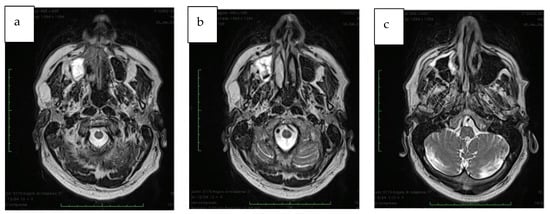

A CT (Computed Tomography) scan was requested at this point, and the results showed bone lysis localized on the palatine and maxillary bone neighboring the lesion. An MR (Magnetic resonance) exam with contrast for the head and neck region showed a residual focal alteration of the hard palate on the right side. The lesion involved posteriorly a part of the soft palate, extending until the borders of the medial part and to the floor of the homolateral maxillary sinus laterally, marking until the oral cavity inferiorly; in the cranial aspect, it was causing a reduction of the aero lumen and blocking the floor of the nasal concha.

The approximate dimensions of the neoplasm: 3.3 cm anteroposterior, 2 cm transverse, and 2.6 cm cranio-caudal. The margins of the lesion were well-defined; however, the involvement of the CNV2 nerve ascendent tract (maxillary division of the trigeminal nerve) (Figure 1a–c) was suspected.

Figure 1.

(a–c) MRI section showing the extension of the maxillary lesion.